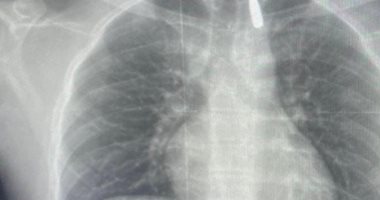

وأوضح الدكتور تامر عبد الله، عميد كلية الطب ورئيس مجلس إدارة المستشفيات الجامعية، أنه في يوم 21 أكتوبر 2025 تمكن فريق من أطباء قسم جراحة القلب والصدر والتخدير والمعاونين من إجراء جراحة دقيقة بالغة الخطورة لأحد المرضى المحجوزين من قطاع غزة، والذي كان قد تعرض لإصابة بطلق ناري في الرأس منذ فترة، استقر المقذوف على إثرها داخل تجويف القفص الصدري قرب الشريان الأورطي، وهو أكبر وأهم شرايين الجسم والمسؤول عن تغذية جميع الأعضاء الحيوية، وأضاف أن الفريق الطبي، رغم دقة الحالة وتعقيدها، نجح في استخراج المقذوف بأمان بعد عملية جراحية نادرة استمرت عدة ساعات داخل المستشفى الجامعي الجديد، حيث خضع المريض بعدها للرعاية الطبية اللازمة، وحالته حاليًا مستقرة وتحت المتابعة الدقيقة من الفريق المختص.